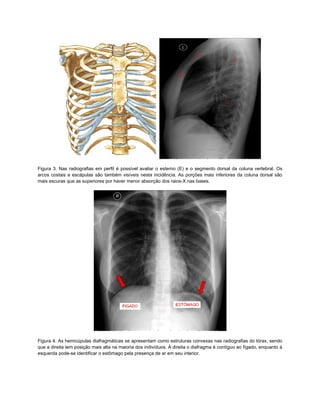

Figura 3. Nas radiografias em perfil é possível avaliar o esterno (E) e o segmento dorsal da coluna vertebral. Os

arcos costais e escápulas são também visíveis nesta incidência. As porções mais inferiores da coluna dorsal são

mais escuras que as superiores por haver menor absorção dos raios-X nas bases.